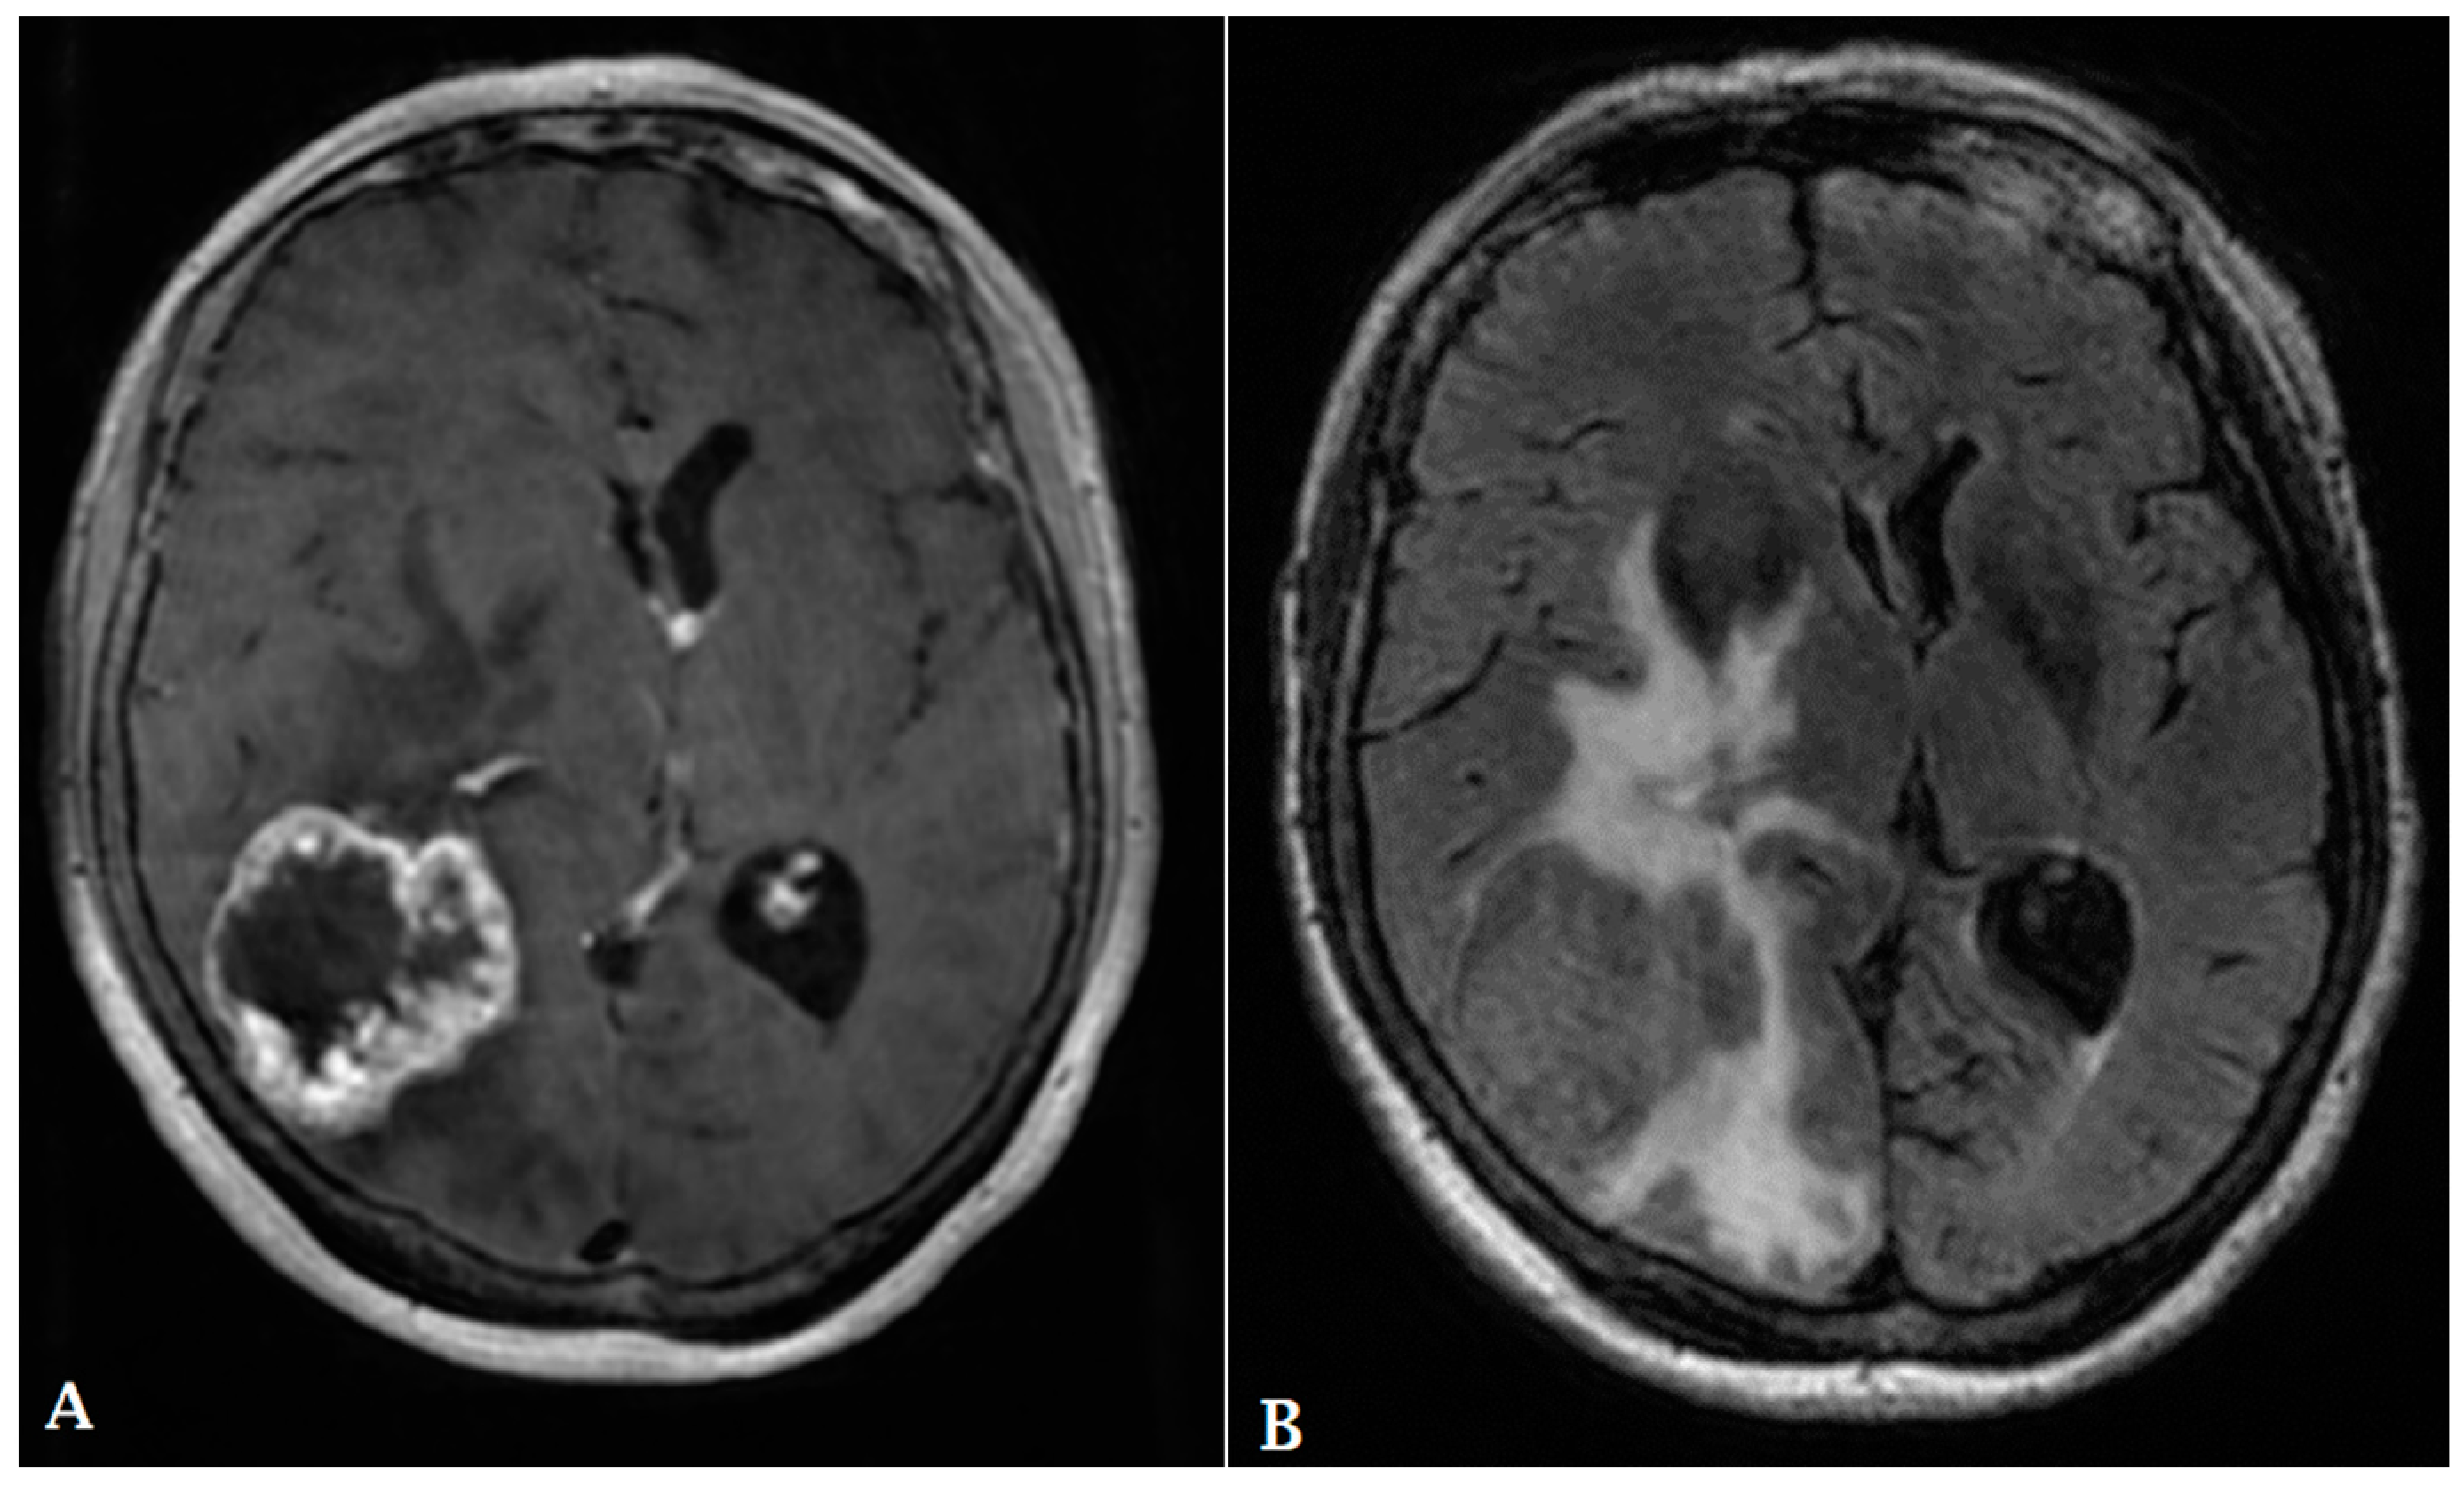

- Hu, L.; Baxter, L.; Smith, K.; Feuerstein, B.; Karis, J.; Eschbacher, J.; Coons, S.; Nakaji, P.; Yeh, R.; Debbins, J.; et al. Relative cerebral blood volume values to differentiate high-grade glioma recurrence from posttreatment radiation effect: Direct correlation between image-guided tissue histopathology and localized dynamic susceptibility-weighted contrast-enhanced perfusion MR imaging measurements. Am. J. Neuroradiol. 2009, 30, 552–558. [Google Scholar] [PubMed]

- Blasel, S.; Jurcoane, A.; Franz, K.; Morawe, G.; Pellikan, S.; Hattingen, E. Elevated peritumoural rCBV values as a mean to differentiate metastases from high-grade gliomas. Acta Neurochir. 2010, 152, 1893–1899. [Google Scholar] [CrossRef]